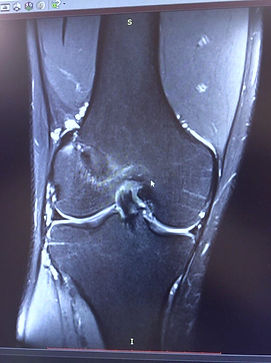

Пациент, возраст 28 лет, подвергся хирургическому вмешательству на передней крестообразной связке (ПКС) один год назад. Трансплантат (ПКС) был выполнен из сложенных втрое сухожилий полусухожильной и сдвоенной нежной мышцы.

На представленной магнитно-резонансной томограмме (МРТ) трансплантат новой передней крестообразной связки демонстрирует полное морфологическое соответствие и структурное подобие с порванной связкой, что свидетельствует о высокой степени интеграции и функциональной состоятельности трансплантата.